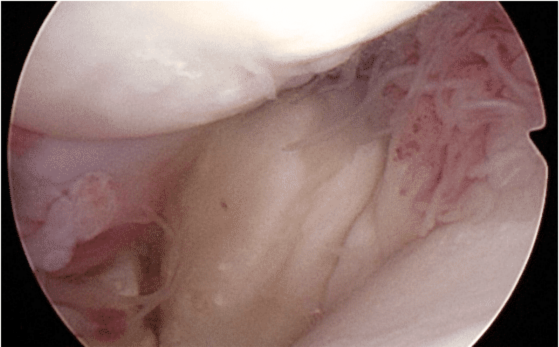

Most cases of supraspinatus tendinopathy do not have mineralization like the case above, and hence are not diagnosed with X-rays (radiographs). Most cases require use of ultrasound, MRI, or diagnostic arthroscopy for diagnostic confirmation. The arthroscopy images below show an enlarged supraspinatus tendon in a canine impinging upon the biceps tendon. The canine supraspinatus is pushing the biceps from right to left.

Most dogs with supraspinatus tendonopathy do not need surgical

treatment, but rather are medically managed with physical rehabilitation, the use of oral medications such as non-steroidal inflammatory drugs (NSAIDs) or intra-articular injections such platelet rich plasma (please see our associated page on PRP and stem cells injections).